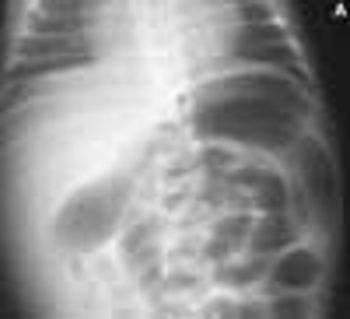

This condition, which accounts for about 30% of cases of intestinal obstruction among neonates, is characterized by the inspissation of thick, tenacious meconium in the bowel. The most common cause is cystic fibrosis; approximately 6% to 20% of infants with cystic fibrosis have meconium ileus. Hyperviscous mucus secreted by abnormal intestinal glands, an abnormal concentrating process in the proximal small intestine, and a deficiency of pancreatic enzymes have been implicated in the pathogenesis. The histologic hallmark is distention of the goblet cells in the intestinal mucosa.

Inspissated, sticky, immobile meconium causes this transient form of distal colonic or rectal obstruction in newborns. The incidence has been estimated at 1 in 500 to 1000 live births. The condition is thought to result from dehydration of the meconium.